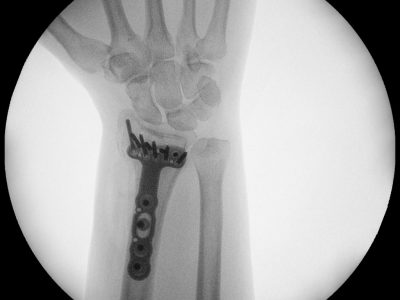

Παρακάτω παρατίθενται ακτινογραφίες καταγμάτων του άνω άκρου που αντιμετωπίζονται με εσωτερική οστεοσύνθεση ή επανορθωτική χειρουργική με αρθροπλαστική.

5. Κατάγματα πηχεοκαρπικής και άκρας χείρας συμπεριλαμβανομένων καταγμάτων σκαφοειδούς και εξαρθρημάτων στα μικρά οστά του καρπού.